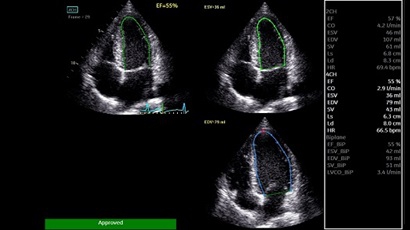

• AUTO 2D EF - режим автоматической недопплеровской количественной оценки глобальной сократительной функции ЛЖ (по Simpson).

• AFI - режим цифровой недопплеровской качественной и количественной оценки региональной сократительной функции ЛЖ.

AUTO 2D EF:

Да

AFI:

Q-ANALYSIS:

ADVQSCAN:

TDI:

LVO Contrast: